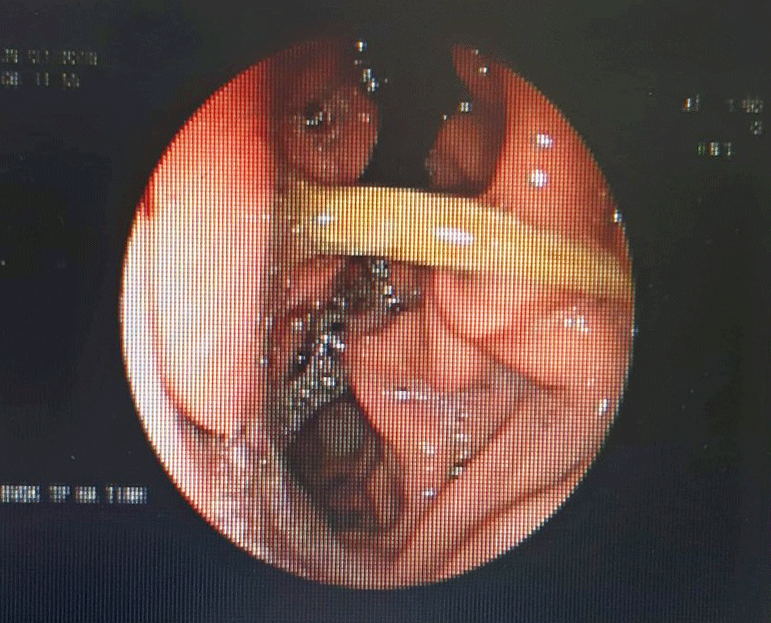

| Hình ảnh nội soi dạ dày bệnh nhân cho thấy que tăm đang nằm ngang dạ dày. (Ảnh: BVCC). |

Sau khi siêu âm, các bác sĩ xác định bệnh nhân này bị nhiễm trùng dạ dày. Trong quá trình nội soi, bác sĩ CKI Hồ Văn Khiêm - Khoa Nội (Bệnh viện đa khoa TP Hà Tĩnh) phát hiện trong dạ dày bệnh nhân có dị vật nằm ngang. Khi bơm rửa sạch thì đó là một que tăm, các bác sĩ sau đó đã soi gắp que tăm ra khỏi dạ dày cho người bệnh.